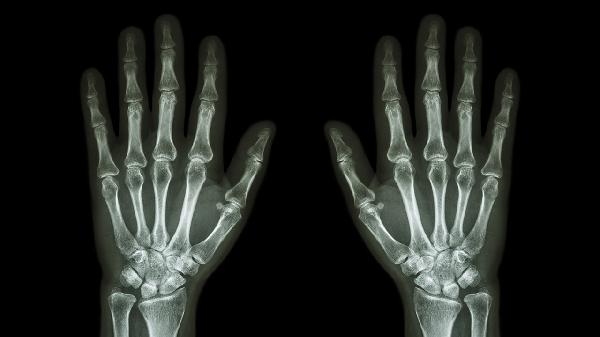

长期关节劳损可能引发骨赘增生,形成坚硬骨性突起。多伴随晨僵、活动受限等症状。X线检查可见关节间隙狭窄。治疗需减少手指负重活动,遵医嘱使用硫酸氨基葡萄糖胶囊、塞来昔布胶囊等药物,严重者需关节清理术。